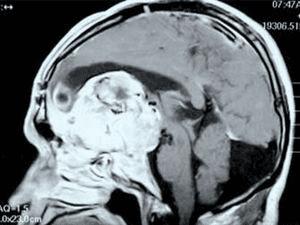

17世纪的法国哲学家有一句名言:“我思故我在”。可以看出,意识在很长时间里都是哲学讨论的话题。现代科学认为,意识是从大脑中数以亿计的神经元的协作中涌现出来的。但是这仍然太笼统了,具体来说,神经元是如何产生意识的?近年来,科学家已经找到了一些可以对这个最主观和最个人的事物进行客观研究的方法和工具,并且借助大脑损伤的病人,科学家得以一窥意识的奥秘。除了要弄清意识的具体运作方式,科学家还想知道一个更深层次问题的答案:它为什么存在,它是如何起源的?

21、记忆是如何存取的?

美好的记忆、悲伤的记忆,关于解方程技巧的记忆,英语单词的记忆,毫无疑问它们都储存在我们的大脑中。但是它们具体在什么部位?

上个世纪50年代,科学家发现大脑中的“海马区”在存储信息的过程中扮演着至关重要的角色——如果切除掉海马区,那么以前的记忆就会一同消失。但是海马区的神经细胞如何把信息固定下来?科学家发现一些分子参与到了记忆的形成。此外,神经细胞突触地形成也与记忆相关联。但是,科学家目前对于记忆的运作机制的了解还不够——而这一机制对于理解我们自身是非常重要的。